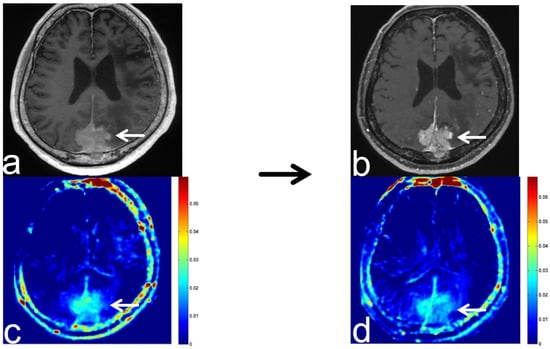

8.1. Radiation Necrosis